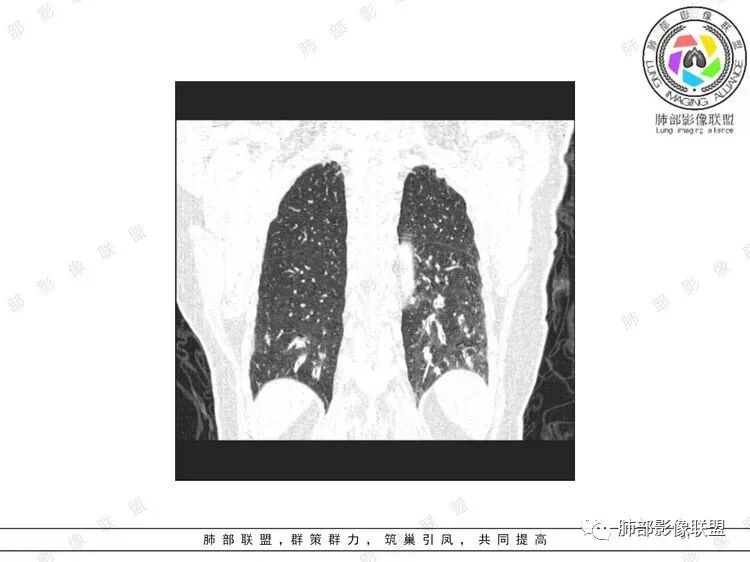

胸CT:双中下肺支气管壁明显增厚,双下肺胸膜下可见实变区。部分病变呈楔形影。

老年女性,咳嗽咳痰低热20天,双肺野散在结节影,随机分布,双肺下叶支气管血管束增粗,支气管管腔狭窄,胸膜下结节斑片影,临床有血尿,痰培养白念阳性,低氧血症。血管炎抗体阴性。从影像看主要侵犯的是血管,血管壁增厚,血管炎抗体阴性不大支持,患者有血尿,考虑膀胱肿瘤引起转移,但是膀胱彩超没发现占位,估计血尿是膀胱炎引起。从影像看考虑侵袭性曲霉菌病?血管炎?实在没有思路。

双肺支气管管壁弥漫性增厚,管腔狭窄,下叶为主,伴多发高密度结节影,边缘模糊,双肺支气管血管束明显增粗,临床症状咳嗽低热,有血尿,首先考虑血管炎

支气管壁增厚,两下肺为主,沿支气管血管束分布斑片状、结节状病变,中轴间质增厚。疾病谱可能有:1.气道来源疾病:结核、曲霉、支原体等;2.间质来源疾病:血管、淋巴系统。结合有血尿,使用激素后尿色变淡、抗生素治疗效果差等病史,考虑血管炎可能性大。

两肺多发小结节,支气管血管束增厚,以下叶为主,病病人血尿,抗炎治疗无效,支持血管炎改变。

影像上:多发结节沿血管分布;双下叶支气管血管束简直增厚,偏血管,支气管通畅

加上结节的分布,支持血管相关病变